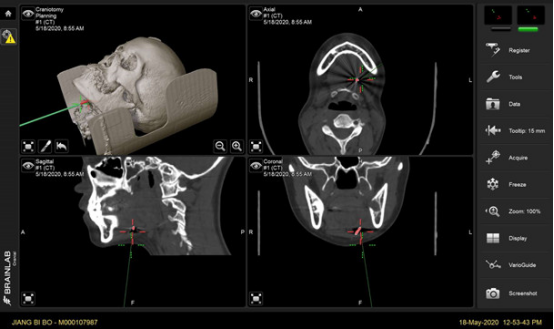

科室经过充分准备,利用数字化外科技术,对患者CT数据进行三维环境下仔细研判,精确测量断针位置,为患者制定细致手术方案。术中,田磊主任团队采用实时导航技术,在距离断针最近的皮肤做小切口,暴露肌肉后层层推进,在连续的导航引导下,终于在下颌舌骨肌中间将这枚细小的断裂车针成功取出,整个手术耗时仅40分钟。

导航技术是将计算机处理的三维模型与实际手术进行交互,通过红外线或激光对手术器械位置的追踪,最大可能提供术区信息,属于计算机增强现实。该技术不仅可以定位准确,提高手术成功率;还可将三维模型与术区匹配,实现个体化手术方案;避开重要解剖结构,降低手术并发症;辅助教学和远程医疗。